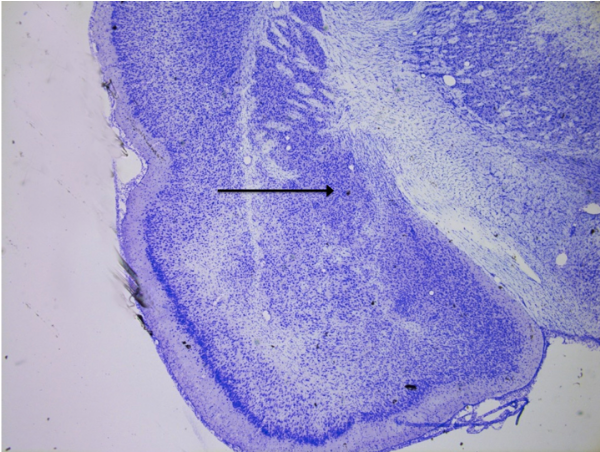

Nucleus accumbens

knowt flashcard image